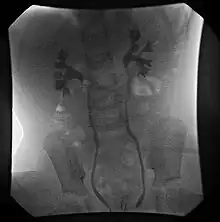

膀胱輸尿管返流的國際分類

- 第I級 - 回流到非擴張的輸尿管。

- 第II級 – 無擴張的回流入腎盂腎盞。

- 第III級 – mild/moderate dilatation of the ureter, renal pelvis and calyces with minimal blunting of the fornices

- 第IV級 – dilation of the renal pelvis and calyces with moderate ureteral tortuosity

- 第V級 – gross dilatation of the ureter, pelvis and calyces; ureteral tortuosity; loss of papillary impressions

The younger the age of the patient and the lower the grade at presentation the higher the chance of spontaneous resolution. Most (approx. 85%) of grade I & II cases of VUR will resolve spontaneously. Approximately 50% of grade III cases and a lower percentage of higher grades will also resolve spontaneously.